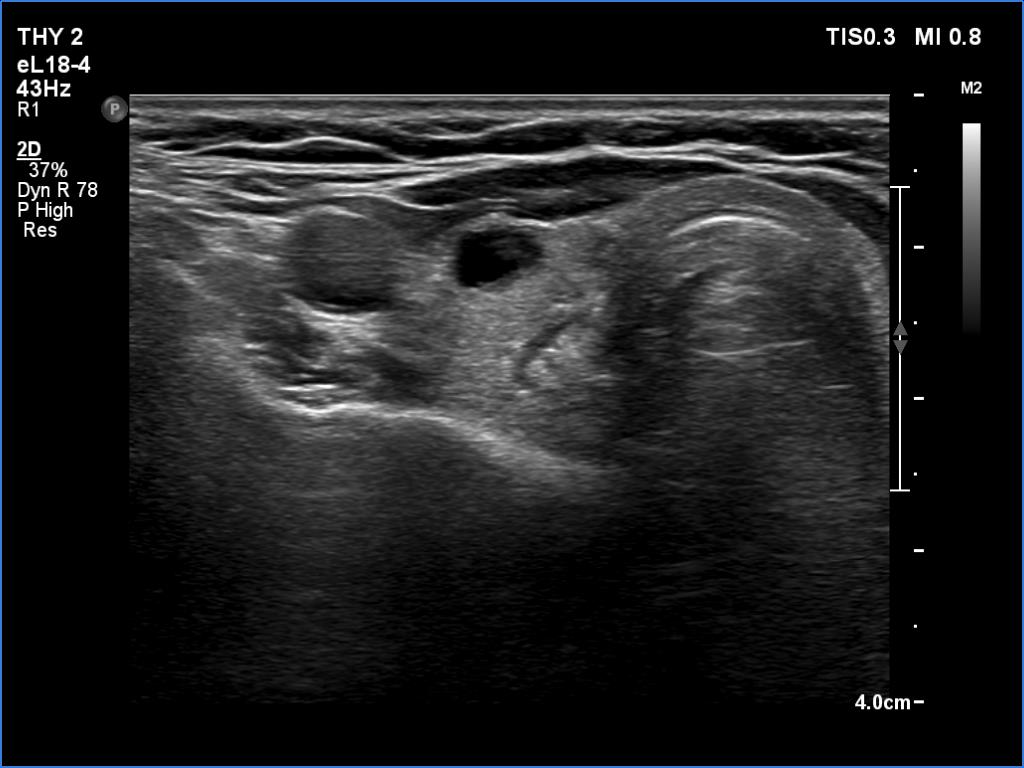

First examination (1st row of images)

Clinical presentation. A 51-year-old woman was referred for aspiration cytology of a thyroid nodule. She was examined because of depression and weight gain. (We met the patient in May 2020 during the COVID epidemic. Her endocrinologist did not meet the patient.)

Palpation: no abnormality.

Ultrasonography. The thyroid was echonormal and had several tiny hypoechoic areas and an echonormal nodule in the lower third of the right lobe. We did not find any lesion of clinical or oncological significance.